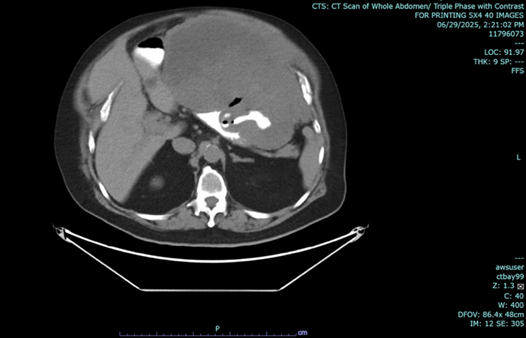

In June 2025, his abdominal CT Scan showed an exophytic lobulated gastric 16.9 x 25 x 17.8 cm mass with central hypodense areas (likely necrosis) arising from fundus and proximal body of stomach, exerting severe mass effect on remaining stomach, pancreas, left hepatic lobes transverse colon, abuts left hemidiaphragm, and distends anterior abdominal wall. Gastroscopy with endoscopic UTS showed a 129.17 x 97.11 mm hypoechoic mass with lobulations at gastric wall adjacent to liver, with some bleeding. Gastric mass biopsy showed GIST, spindle cell type, mitotic rate 4 per 5 mm sq, low grade, CD34+, CD117+, Desmin-, DOG1+, HER-, S100-, Ki67-, 21-30% proliferative index, no loss of nuclear expression of MMR proteins.

Figure 1 a-c: June 29, 2025 Abdominal CT Scan showing hypodense mass.